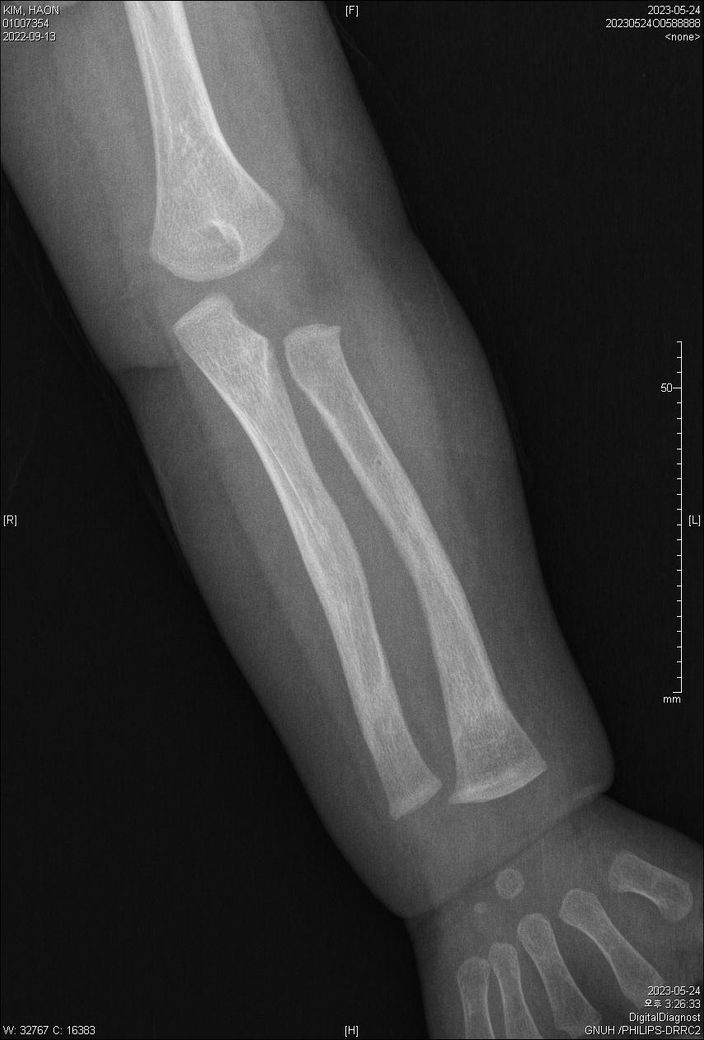

23.5.24 X-ray입니다.

양팔이 골절이 되었었는데요,

가골형성 시기인지,

재형성(리모델링) 시기인지 궁금합니다.

• 2번 째 사진

사진상으로 골유합이 잘 진행중입니다. 리모델링은 추후 수개월에서 수년까지 걸쳐서 일어나서 특정할순 없습니다.